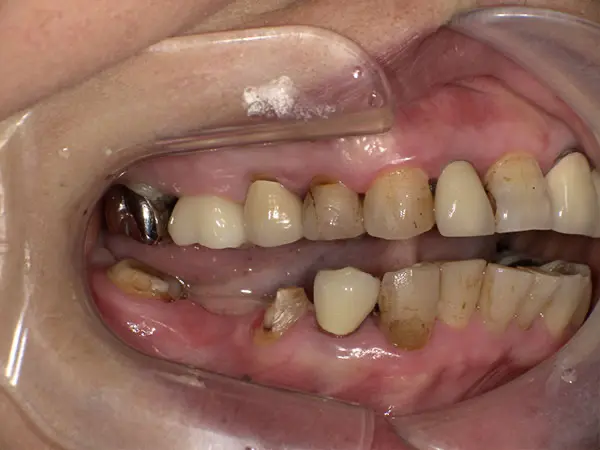

叢生

術前側貌

術前正面

術後側貌

術後正面

術中上顎

術中下顎

| 主訴 | 歯のがたつき、出っ歯 |

| 初診年齢 | 23歳 |

| 治療内容・装置 | 自費、上裏側・下表側、アンカースクリュー |

| 抜歯・非抜歯 | 抜歯 |

| 治療期間 | 2年3か月 |

| 費用 | 1,383,800円(税込) (相談料、検査料、診断料、動的治療費、保定期間料、抜歯代、アンカースクリュー費等含む) |

| 治療のリスク・副作用 | 歯の移動に伴う痛み 上下顎前歯部の歯根吸収 装置による口内炎 ブラッシング不良によるむし歯・歯肉炎 |